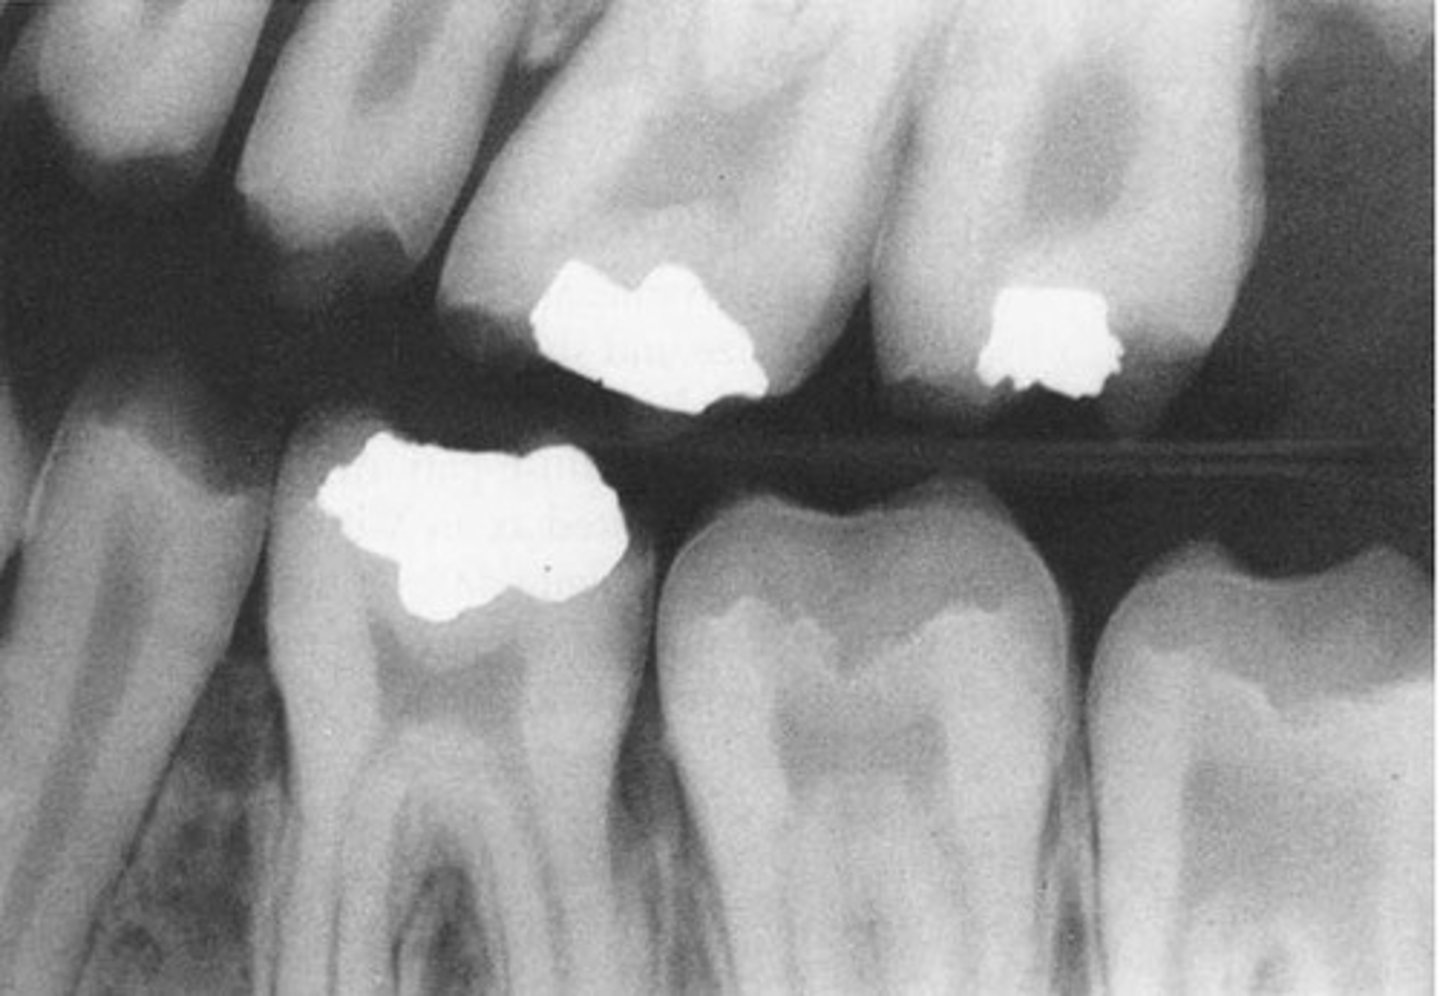

Multiple questions about eruption and looking at BW to see if its normal

prim calcification

perm calcification

prim eruption

perm eruption

prim calcification:

A 14

D 15

B 16

C 17

E 18

perm calcification:

6 - birth

1, L2, 3 - 6 mo

U2 - 12 mo

4 - 18 mo

5 - 24 mo

7 - 30 mo

prim eruption:

8 9 16 13 26

6 10 17 14 23

perm eruption:

7 8 11 10 10.5 6 12 17

6 7 9 10 11 6 11 17